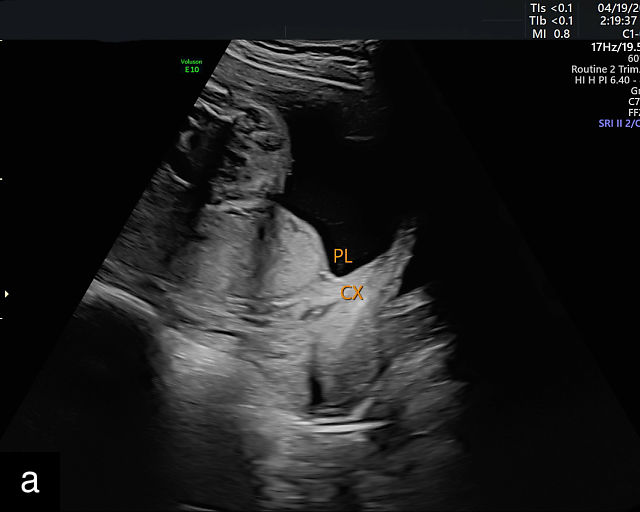

5

Placenta previa and low-lying placenta. (a) Transabdominal grayscale ultrasound image suspicious for placenta previa. The placenta (PL) appears to overlie the internal cervical os (CX). Note the time stamp: 2:19:37. (b) Transvaginal ultrasound of the same patient taken approximately 50 minutes later. Note the time stamp: 3:10:25. The internal os and the lower placental edge are both clearly seen, and the placenta does not overlie the internal os. Because the lower placental edge is 1.93 cm from the internal os, it will likely resolve by the third trimester. (c) Transabdominal grayscale ultrasound of placenta previa. The placenta (p) covers the cervix, but the cervix, especially the internal os, cannot be visualized due to shadowing. (d) Transabdominal grayscale ultrasound of placenta previa. The placenta (p) covers the cervix (c) but shadowing obscures adequate visualization. The internal os is indicated by the arrow. (e) False-positive image of placenta previa on transabdominal grayscale ultrasound. The bladder (b) is full, pushing the anterior and posterior walls of the lower uterine segment (ls) together making it appear that the placenta (p) overlies the internal os of the cervix. In reality, the line depicted by the arrowheads is where the anterior and posterior walls of the lower segment are in proximity to each other. The cervix is much lower and is obscured by shadowing (c). (f) Transabdominal grayscale ultrasound image of placenta previa. The placenta (p) covers the cervix (c), but the cervix, especially the internal os, cannot be visualized due to shadowing. b, bladder. (g) Transvaginal grayscale ultrasound image of placenta previa. The placenta (p) completely covers the internal os (arrow) of the cervix (c). The internal os can be seen clearly. h, fetal head. (h) Transvaginal grayscale ultrasound image of posterior low-lying placenta (p). The lower placental edge is clearly seen and is 1.56 cm from the internal os (arrow) of the cervix (c). The placental edge and the internal os are clearly seen. h, fetal head. (i) Transvaginal grayscale ultrasound image of a posterior placenta previa (p). The internal cervical os is clearly seen (arrow). c, cervix. (j) Transvaginal grayscale ultrasound image of an anterior placenta previa (p). The internal cervical os is clearly seen (arrow). c, cervix; h, fetal head. (k) Transvaginal grayscale ultrasound image of a posterior placenta that was thought to be low-lying on transabdominal sonography but could not be adequately assessed. This examination clearly shows the lower edge of the placenta (p) to be 2.18 cm from the internal os (arrow) of the cervix, firmly establishing that the placenta is not low-lying and allowing the patient to undergo labor safely and deliver vaginally. c, cervix. (l) Transvaginal grayscale ultrasound image of placenta previa. The placenta (p) completely covers the internal os (arrow) of the cervix (c). The internal os can be seen clearly.

Most cases of placenta previa will be suspected prenatally by transabdominal ultrasound.49 However, this approach has several limitations and may be inaccurate.72,73,74 because the relationship between the placenta and the internal cervical os may be difficult to assess by transabdominal ultrasound.72,73,74 The bladder may be full, pushing the anterior and posterior walls of the lower uterine segment together, falsely creating the impression of a placenta previa (Figure 5e).61 There may be considerable shadowing, including by the fetal presenting part, which may limit the accuracy of transabdominal ultrasound (Figure 5d,f).75 Posterior placentas may be more difficult to assess.

Transvaginal ultrasound overcomes these limitations (Figure 5g–l).72,73,74,76 The probe is inserted into the vagina and therefore is closer to the region of interest.51,61 In addition, transvaginal transducers have higher frequencies and superior resolution compared to transabdominal transducers. Transvaginal ultrasound is safe and is not associated with increased bleeding.72,73,74,75,76 As such, transvaginal ultrasound should be the imaging modality of choice whenever there is suspicion of placenta previa.49,67,77